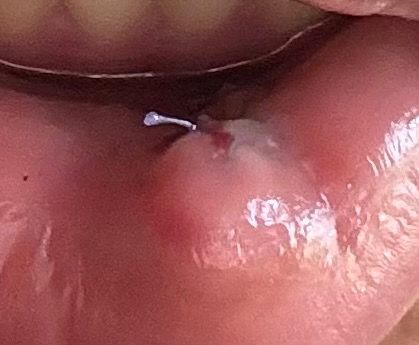

육아종 제거 수술을 화요일에 진행하였는데 수술 후 가장 크게 벌어져있던? 부위에 흰색 이물질같은 것이 생겼습니다

순서대로 수술 다음날 수요일, 금요일, 토요일입니다.

• 1번 째 사진

사진상으로 보면 잇몸이 아물면서 생기는 자연스러운 현상이니 너무 걱정하지 않으셔도 될것같습니다.

잇몸 흡수를 받게 되면 해당 부의 가피등이 형성될 수 있습니다. 이런 카피들은 흰색으로 보이게 되는데 크게 문제가 되지 않습니다.